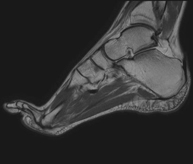

Exploració per estudiar aquesta articulació i les lesions freqüents de lligaments (esquinços), així com l'afectació d'altres estructures, com el cartílag o l'os. També és de gran utilitat per diagnosticar alteracions al tendó d'Aquil·les (tendinitis o trencaments). La durada aproximada és de 20 minuts. No utilitza radiació ionitzant. - RM de Peu

Exploració per a l'estudi de lesions en tendons, músculs i petites articulacions. Permet valorar amb eficàcia les lesions al cartílag. També és de molta utilitat per completar l'exploració ecogràfica prèvia. No empra radiació ionitzant. Té una durada aproximada de 20 minuts. - Artro-RM d'Espatlla